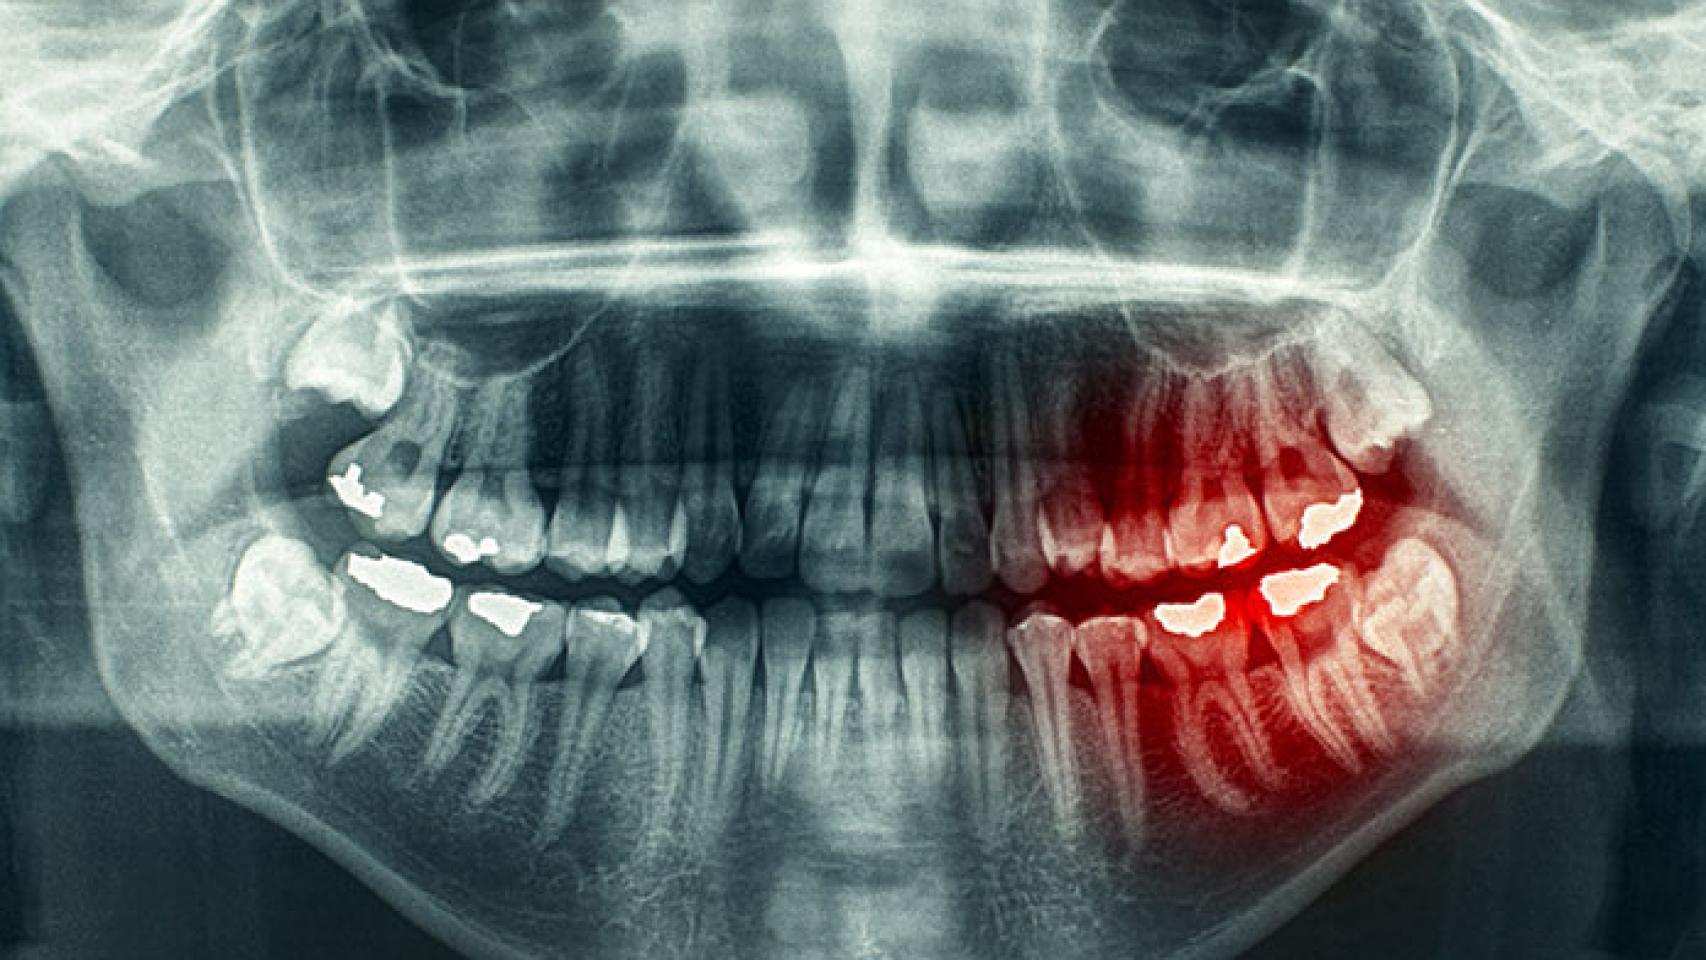

El tumor de orofaringe provocado por este virus, eso sí, se manifiesta de una manera más temprana, como explica la SEORL-CCC en su página web, entre los 45 y los 50 años, en concreto. Estos tumores "tienen especial predilección por determinadas zonas de la faringe como las amígdalas palatinas y la base de la lengua", explica el organismo. "Sin embargo, el VPH puede estar en las cuerdas vocales y buena parte de la lengua y la boca y no genera cáncer, según lo que sabemos. Sólo lo hace en algunas localizaciones", concreta Sistiaga.